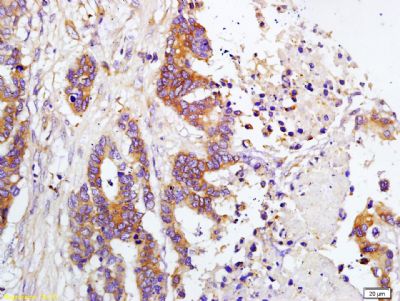

| 产品图片 | ![]() Sample: Lane1: Brain(Mouse) Lysate at 30 ug Lane2: Liver (Mouse) Lysate at 30 ug Primary: Anti-TIMP-1 (bs-0415R) at 1:200 dilution; Secondary: HRP conjugated Goat Anti-Rabbit IgG(bs-0295G-HRP) at 1: 3000 dilution; Predicted band size : 21kD Observed band size : 26kD ![]() Tissue/cell: human gastric carcinoma; 4% Paraformaldehyde-fixed and paraffin-embedded; Antigen retrieval: citrate buffer ( 0.01M, pH 6.0 ), Boiling bathing for 15min; Block endogenous peroxidase by 3% Hydrogen peroxide for 30min; Blocking buffer (normal goat serum,C-0005) at 37℃ for 20 min; Incubation: Anti-TIMP-1 Polyclonal Antibody, Unconjugated(bs-0415R) 1:200, overnight at 4°C, followed by conjugation to the secondary antibody(SP-0023) and DAB(C-0010) staining ![]() Tissue/cell: human colon carcinoma; 4% Paraformaldehyde-fixed and paraffin-embedded; Antigen retrieval: citrate buffer ( 0.01M, pH 6.0 ), Boiling bathing for 15min; Block endogenous peroxidase by 3% Hydrogen peroxide for 30min; Blocking buffer (normal goat serum,C-0005) at 37℃ for 20 min; Incubation: Anti-TIMP-1 Polyclonal Antibody, Unconjugated(bs-0415R) 1:200, overnight at 4°C, followed by conjugation to the secondary antibody(SP-0023) and DAB(C-0010) staining ![]() Tissue/cell: human colon carcinoma; 4% Paraformaldehyde-fixed and paraffin-embedded; Antigen retrieval: citrate buffer ( 0.01M, pH 6.0 ), Boiling bathing for 15min; Block endogenous peroxidase by 3% Hydrogen peroxide for 30min; Blocking buffer (normal goat serum,C-0005) at 37℃ for 20 min; Incubation: Anti-TIMP-1 Polyclonal Antibody, Unconjugated(bs-0415R) 1:200, overnight at 4°C, followed by conjugation to the secondary antibody(SP-0023) and DAB(C-0010) staining ![]() Tissue/cell: rabbit liver tissue; 4% Paraformaldehyde-fixed and paraffin-embedded; Antigen retrieval: citrate buffer ( 0.01M, pH 6.0 ), Boiling bathing for 15min; Block endogenous peroxidase by 3% Hydrogen peroxide for 30min; Blocking buffer (normal goat serum,C-0005) at 37℃ for 20 min; Incubation: Anti-TIMP-1 Polyclonal Antibody, Unconjugated(bs-0415R) 1:200, overnight at 4°C, followed by conjugation to the secondary antibody(SP-0023) and DAB(C-0010) staining |